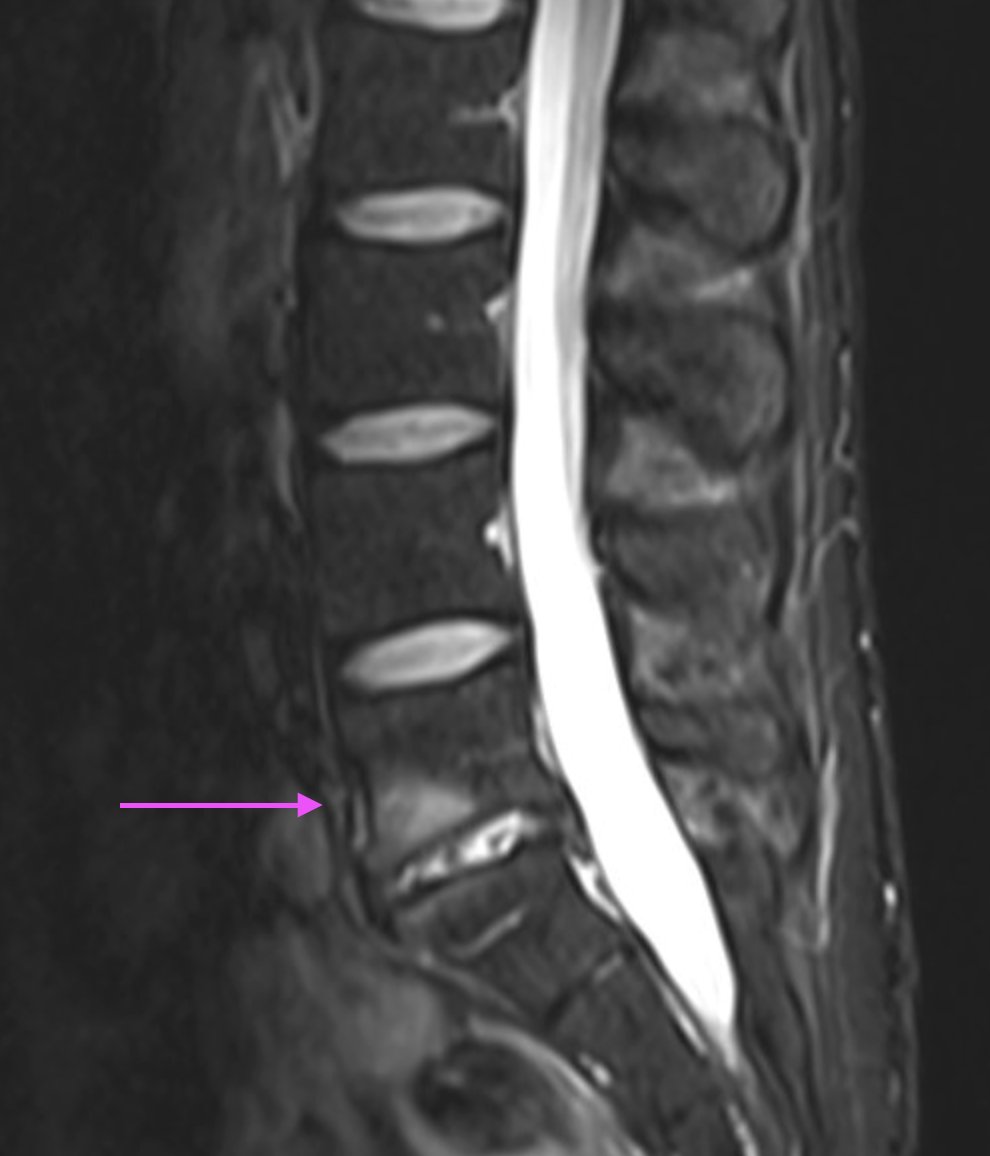

Consent ✅ Runner, X fit, cyclist R inferior gluteal pain radiating into posterior thigh & calf for 2 years Provoked by sitting, striding out, inclines MRI pelvis - mild proximal hamstring tendinopathy MRI LSp - R sided mild disc bulge L4/5 Battery of high hamstring tests